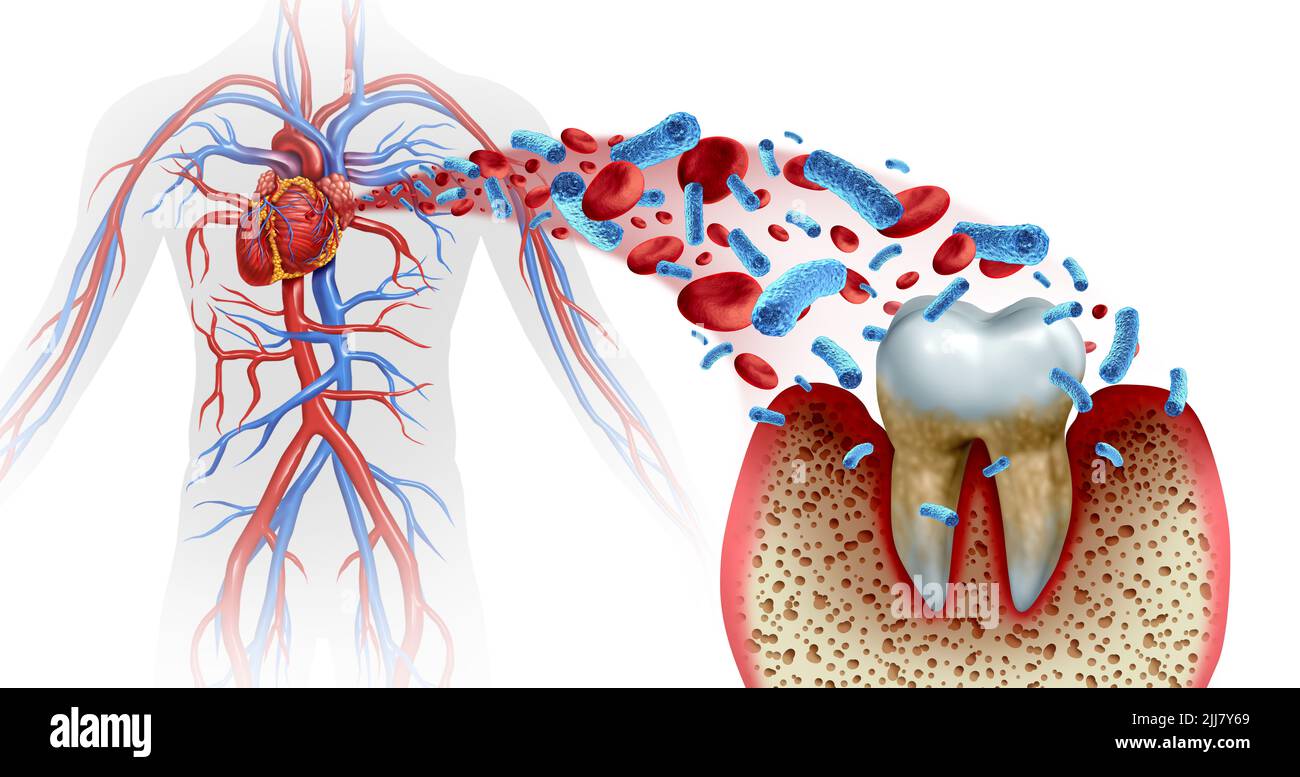

Tooth decay and heart disease as an unhealthy molar with periodontitis due to poor oral hygiene health problem as a bacteria infection in the blood. Stock Photohttps://www.alamy.com/image-license-details/?v=1https://www.alamy.com/tooth-decay-and-heart-disease-as-an-unhealthy-molar-with-periodontitis-due-to-poor-oral-hygiene-health-problem-as-a-bacteria-infection-in-the-blood-image475918753.html

Tooth decay and heart disease as an unhealthy molar with periodontitis due to poor oral hygiene health problem as a bacteria infection in the blood. Stock Photohttps://www.alamy.com/image-license-details/?v=1https://www.alamy.com/tooth-decay-and-heart-disease-as-an-unhealthy-molar-with-periodontitis-due-to-poor-oral-hygiene-health-problem-as-a-bacteria-infection-in-the-blood-image475918753.htmlRF2JJ7Y69–Tooth decay and heart disease as an unhealthy molar with periodontitis due to poor oral hygiene health problem as a bacteria infection in the blood.